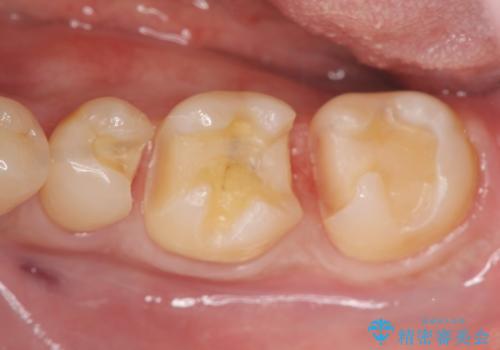

保険適応の白い詰め物レジンインレー下に再発した大きな虫歯治療

- 以前治療した歯の違和感、しみる感じの改善を求めて来院されました。

保険適応の素材、レジン素材による修復が行われていますが、X線写真より修復物の下には透過像(黒い影)が認められ、症状からも虫歯の再発が強く疑われます。